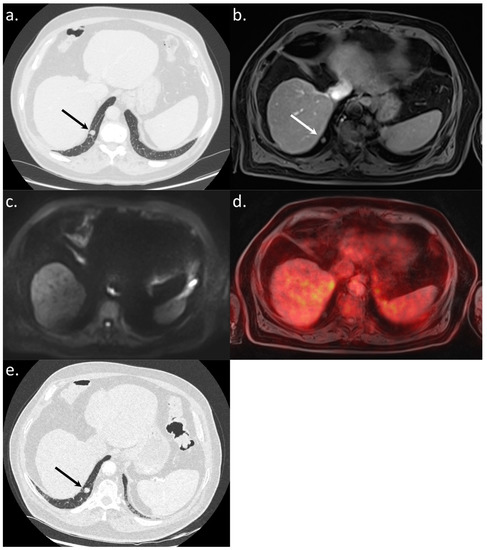

All 14 metastatic sites were correctly identified on the WB-PET/MRI, although only 7 of 16 individual pulmonary metastases (44%) were seen (Figure 2). On the CT-CAP/liver MRI dataset, six metastatic sites were correctly identified (6/14; 43%), resulting in a significantly lower sensitivity (43% vs. 100%, p = 0.002). Notably, all 10 individual bone metastases were missed on the CT-CAP/liver MRI (Figure 3), as well as two mediastinal lymph nodes (Figure 4) and one retroperitoneal lymph node involvement (Figure 3).

The WB-PET/MRI lead to changes in therapeutic management in 10 of 104 patients (9.6%). Metastatic lesions were identified by the WB-PET/MRI in two BCLC stage C patients referred before liver transplantation (Figure 3) and in five BCLC stage C patients referred before TARE (Figure 2 and Figure 4).

Figure 2. A 56-year-old patient referred to WB-PET/MRI before TARE. The CT-CAP (a) showed a solitary rounded 7 mm-size lung nodule (arrows). The WB-PET/MRI confirmed an infracentimetric lung nodule visible on morphologic sequences (T1-weighted after gadolinium injection) (b) with hyperintensity on b800 s/mm2 DWI (c) and 18F-FDG hypermetabolism (d) leading to the diagnosis of lung metastasis. The followup CT scan (e,f) performed three months after the WB-PET/MRI showed a significant progression of the number and size of lung nodules, confirming the metastatic status.